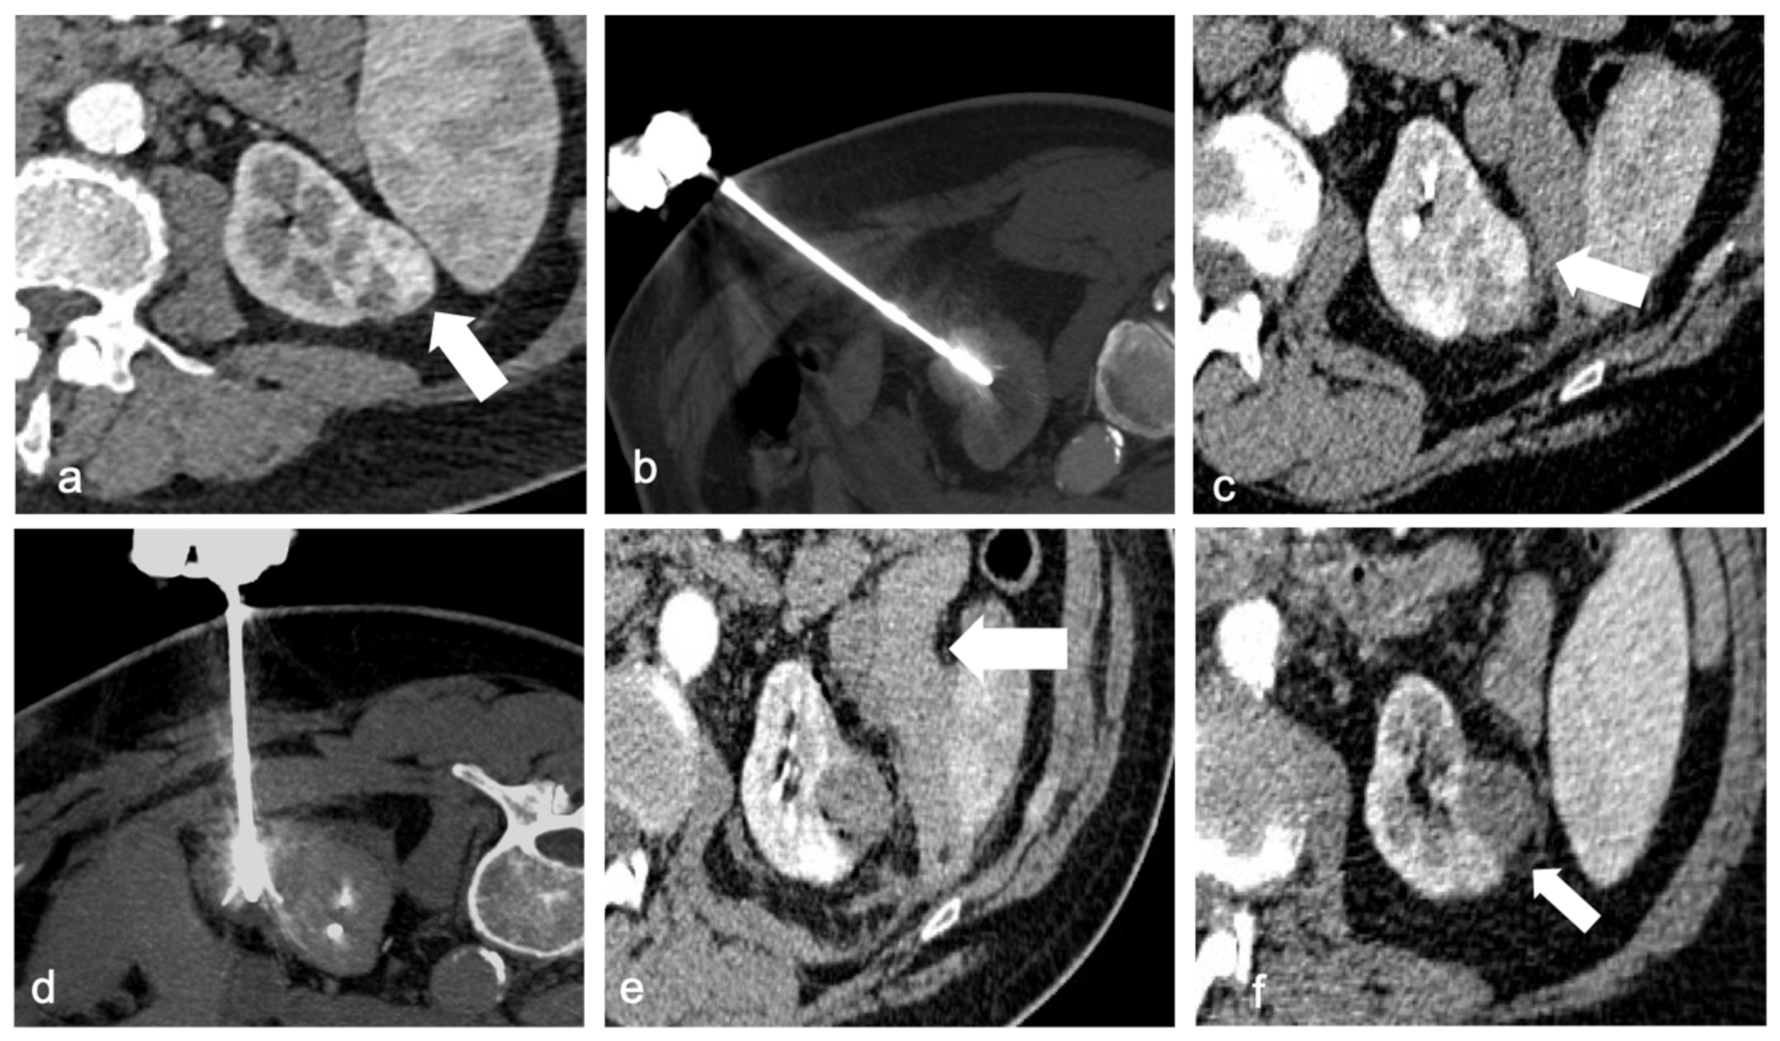

The technical success rate for ablations of T1a (≤4 cm) lesions is close to 100%, and the primary local control is excellent (Figure 2). The outcomes of T1a lesions treated with RF, CA, or MW ablation were comparable to those of total or partial nephrectomy (5-year cancer-specific survival 95–98%), but there were fewer post-procedural complications, unplanned hospital readmissions, decreased 30- and 90-day mortality, and a lower risk of long-term renal insufficiency [52].

Figure 2.

A 67-year-old man with a 34 mm renal cell carcinoma in the left kidney. Axial contrast-enhanced CT (a) demonstrates a heterogeneously enhancing mass (arrow). RF ablation was performed with multitined expandable electrods (b), but post-procedural contrast-enhanced CT revealed areas of enhancement in the mass (arrow) compatible with residual disease (c). A second target positioning was performed to achieve a complete ablation (d). Post-procedural CT shows no enhancement of the ablated lesion and a small hematoma (arrow, (e)). Follow-up CT after 4 weeks revealed no evidence of residual or recurrent disease (arrow) and partial reabsorption of the hematoma (f).